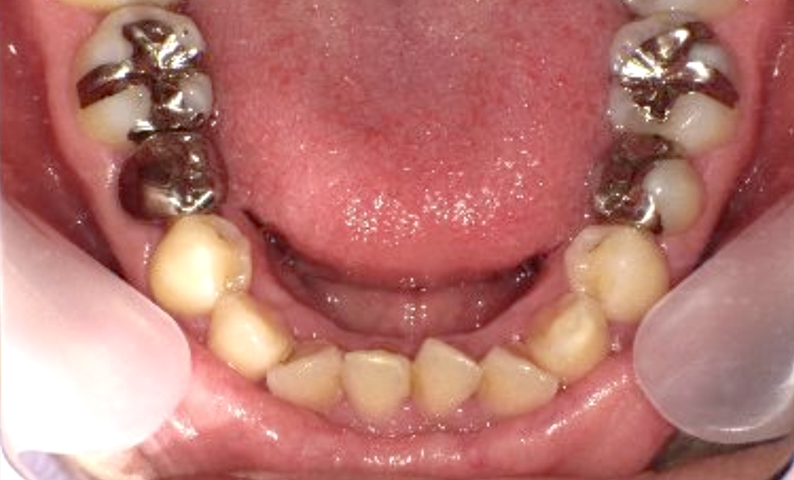

症例_004 下顎だけの部分矯正

治療期間:7ヶ月金額:24万円+税男性前歯のガタガタ下の前歯だけ

| Before | After |

|---|---|

|